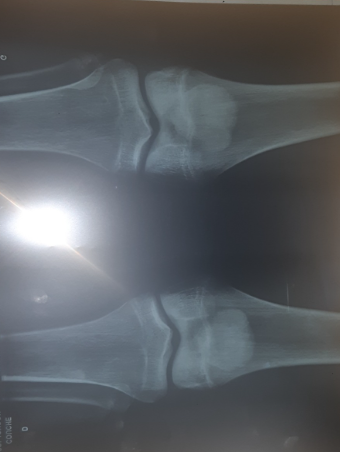

Are my growth plates still open?